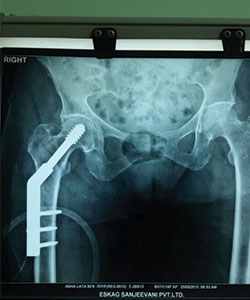

Case 1: Hip Fracture (Intertrochanteric Fracture)

70 Years female presented with right hip fracture following a fall in the bathroom

XRAY - 2

post operation X-RAY (fracture fixed with Dynamic hip screw)